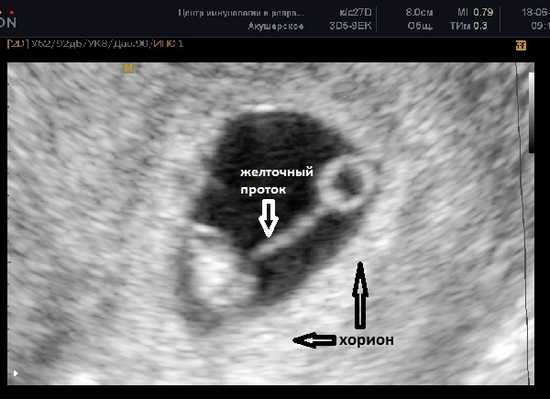

Фото УЗИ плода при беременности 7-8 недель

Расстояние между эмбрионом и желточным мешком постепенно увеличивается и становится хорошо различим желточный проток (ductus vitellinus), соединяющий между собой желточный мешок и кишечник эмбриона. Так же, как и желточный мешок, проток на более поздних сроках запустевает и рассасывается, но если это не происходит по каким-то причинам, то у человека формируется слепое выпячивание стенки подвздошной кишки - дивертикул Меккеля.

До этого срока хорион имеет кольцевидную форму, окружает плодное яйцо со всех сторон и пока ещё нельзя сказать к какой стенке матки прикрепился эмбрион.

В случае монохориальной двойни ещё не видно амниотических оболочек и при наличии двух желточных мешков всё ещё нельзя сказать является ли данная беременность моно или диамниотической. Если плодное яйцо содержит два желточных мешка и два плода с наличием сердечной активности, в последующем количество амниотических полостей может быть больше, чем количество плацент (монохориальная диамниотическая) или одинаковым (монохориальная моноамниотическая). В этом случае точно определить амниональность возможно после 8 недель, когда амниотические оболочки начинают четко визуализироваться.

ЧСС эмбриона 130-160 ударов в минуту.

СВД плодного яйца 24-30 мм, КТР эмбриона 9-15 мм.